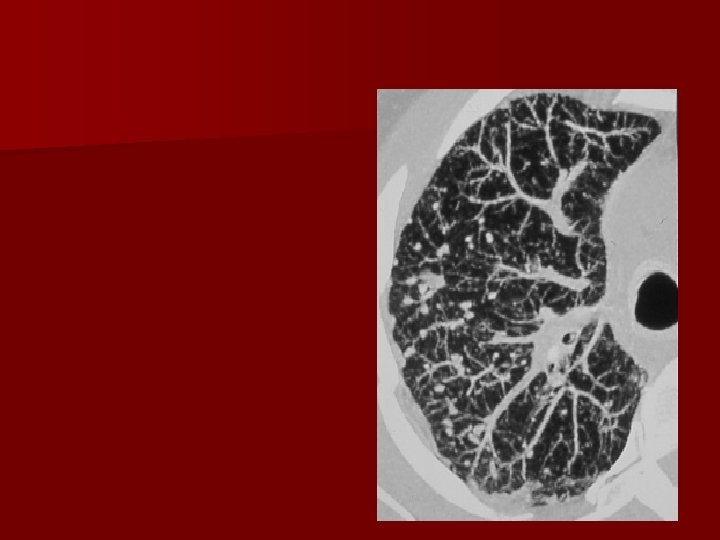

Caso clinico n n n 29 anni Donna Lieve ipertermia Artralgie Non fumatrice Non sintomi respiratori

Ipotesi diagnostiche 1. 2. 3. 4. 5. Linfoma TB BAC Sarcoidosi Vasculite